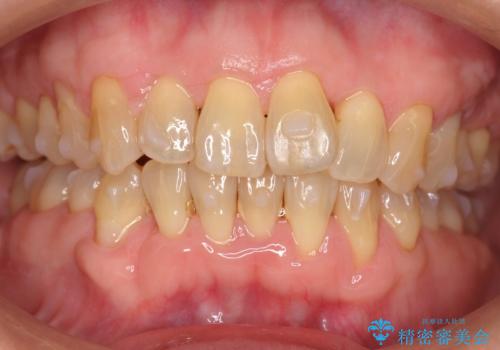

前歯のがたつき インビザラインで抜歯矯正

- 前歯のがたつきを主訴に来院。

右下の犬歯が歯ぐきが痩せて、歯肉退縮しておりそれを抜歯しました。

上の前歯はIPRを行なっています。

右下の犬歯の1本抜歯で最小限の抜歯で並べることができました。